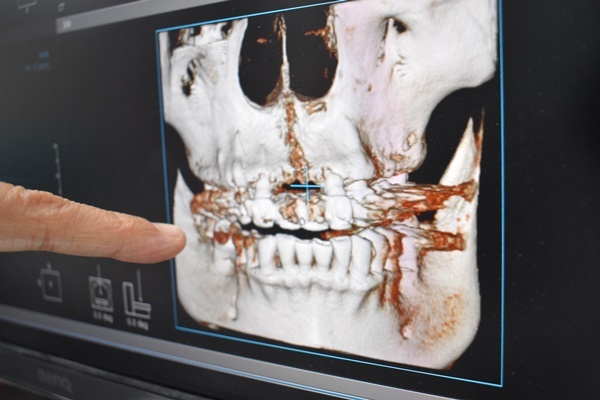

醫師會先在首次看診先拍攝X光片及斷層掃描

X光片是2D顯影

斷層掃描是3D顯影可以看到皮膚下骨頭層次

先用2D確認牙齒骨頭缺損情況及周圍鄰牙健康問題

再看3D來評估缺損牙齒位置需要補上多少人工骨粉才能使植牙穩固